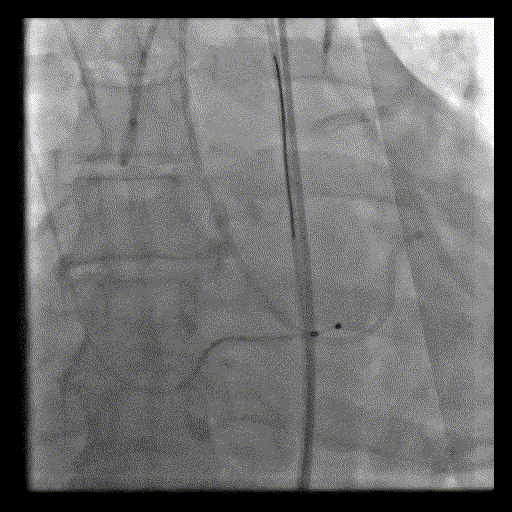

置入左室加硬导丝